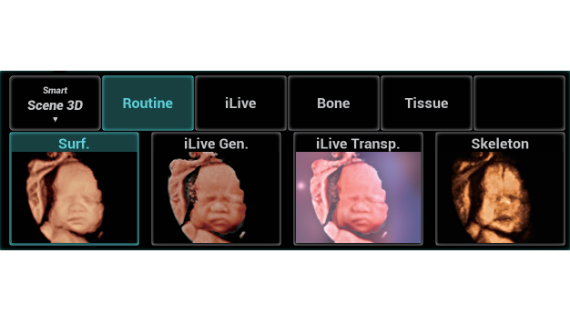

Nuewa I9? ??? ???? ?? ??? ?? ??? ???? ?? ??? ???? ???? ??? ?????. ??? ??? ??? ?? ????? ?? ???? ???? ???? ???? ??? ???? ??? ??? ???? ??? ???? ??? ?? ?????.